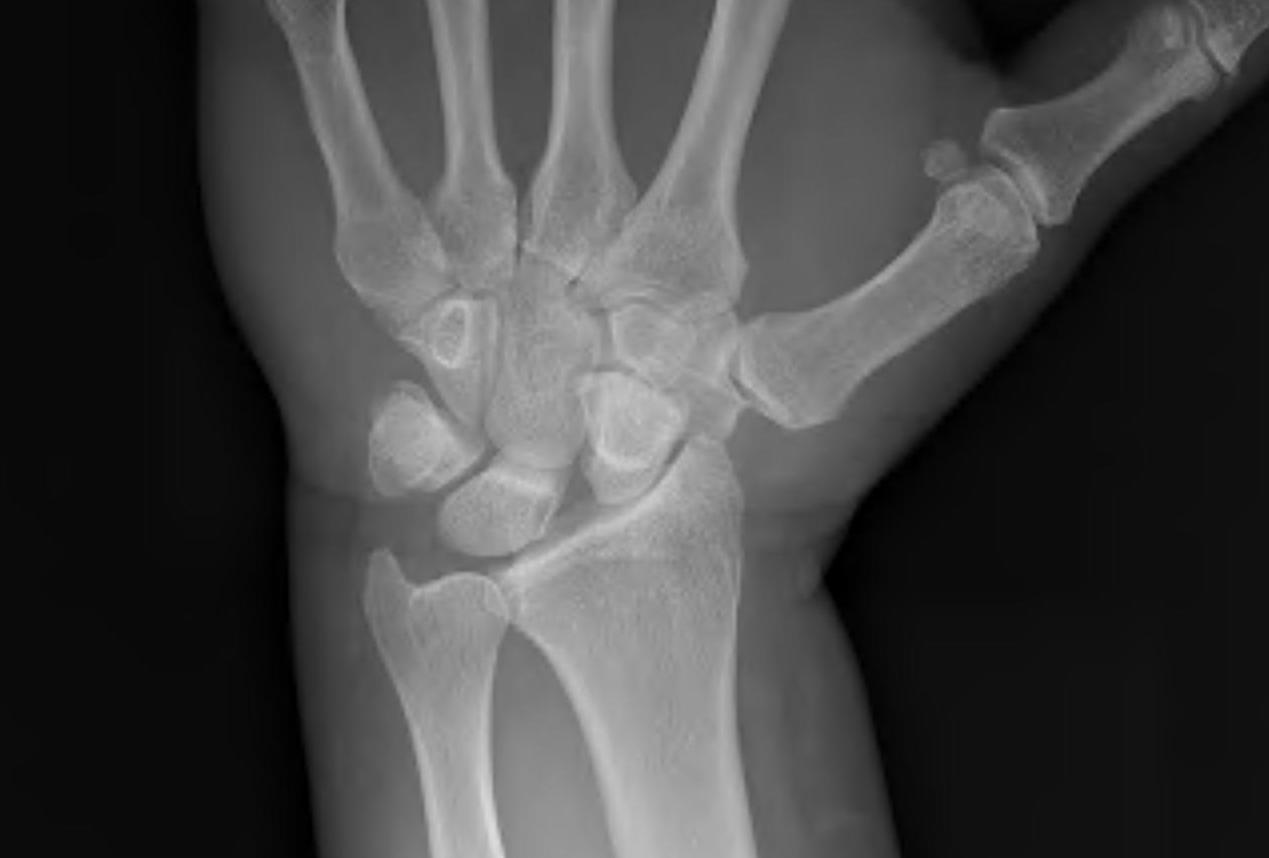

AP

Terry Thomas sign

- increased scapholunate interval

- > 3 mm compared with other side

Stress views

- bilateral wrists clenched

- in ulnar deviation

- in radial deviation

- may show Terry Thomas sign

Cortical Ring sign

- end-on view of cortex of distal pole of scaphoid

Scaphoid shortened

- due to palmar flexion